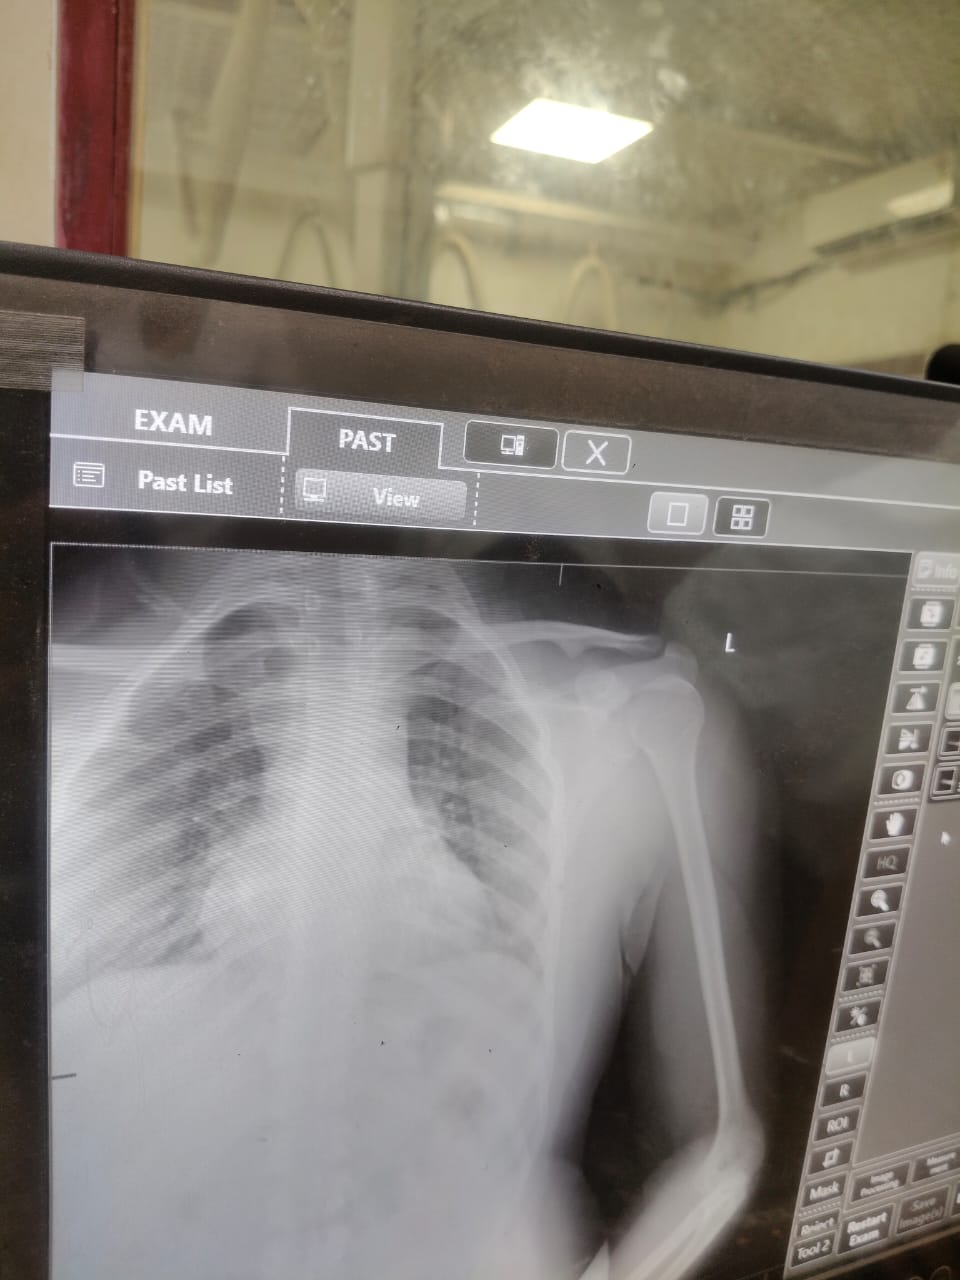

सुल्तानपुर | स्वशासी राजकीय चिकित्सालय में भले ही करोड़ों खरबों रुपए खर्च करके 600 बेड मरीजों के लिए तैयार हुआ है लेकिन इसके बावजूद स्वास्थ सेवा की गाड़ी बेपटरी हो जा रही। थके मन से कार्य करने वाले अफसर भी इस समस्या से अंजान हैं।नतीजन दर्जनों मरीज को निराश होकर वापस लौटना पड़ रहा है।कुछ मरीजों को एंड्रॉयड फोन से फोटो खींचकर रिपोर्ट दी जा रही।

जबकि फ़िल्म नही निकलने से दर्जनों मरीज परेशान हैं। दुर्घटना में घायल होने वाले अस्थि रोग से संबंधित पेशेंट जब एक्सरे रूम में जा रहा है ।तो वहां पर एक्सरे का प्रिंट नही निकल रहा। बताया जा रहा है की मशीन में एक बार फिर से फाल्ट आ गई है।

इसके पहले भी कई बार तकनीकी खामियों के चलते सुदूर क्षेत्रों से आए हुए मरीजों को निराश होकर वापस लौटना पड़ा है ।इस बाबत प्राचार्य महोदय ने बताया कि मामले की जानकारी करके बताते हैं ।

जब दोबारा फोन किया गया तो उन्होंने खबर को प्रमाणिक बताया ।कहा कि तकनीकी फाल्ट आ जाने के कारण यह समस्या आई है ।

शीघ्र ही उसे दुरुस्त करवाया जाएगा।